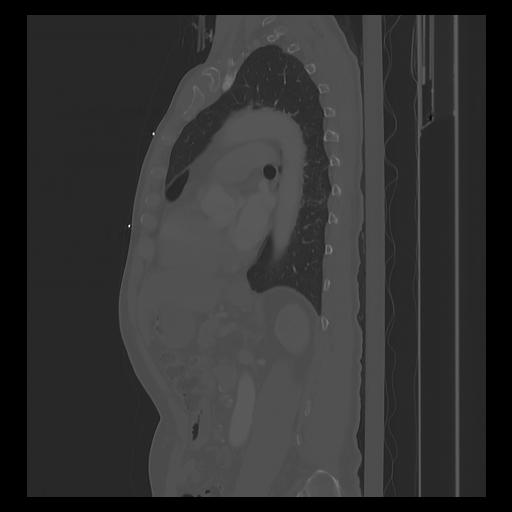

33 PULMON,CE,Sagittal,3.000,PULMON,Sagittal,